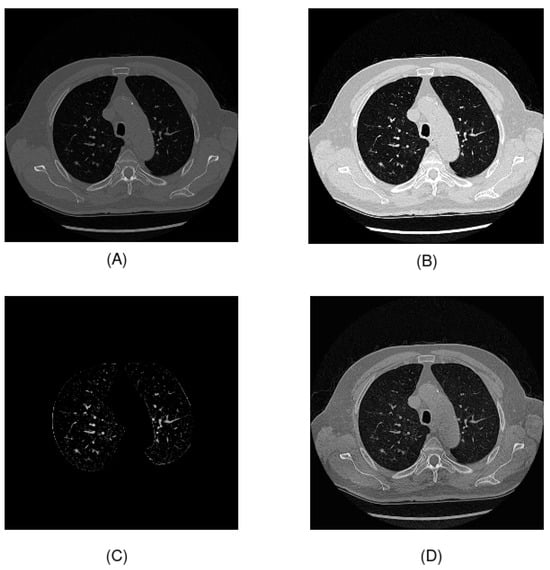

Regarding preprocessing, numerous techniques are available for working with CT scans. In this study, we used the two preprocessing techniques for Hounsfield units and contrast enhancement proposed in the original article by Chaudhry et al. [24] and two proposed techniques based on lung segmentation and thresholding and on contrast-limited adaptive histogram equalization (CLAHE) for contrast enhancement. The application of these four techniques on a CT image is shown in Figure 2:

Figure 2. Preprocessing techniques used in this study: (A) Hounsfield units preprocessing; (B) windowing; (C) U-Net R231 and thresholding; (D) CLAHE.

First, we applied preprocessing of the Hounsfield units. The raw pixel values of DICOM images are scanner values ranging from 0 to 4095. These values need to be transformed into Hounsfield units for clinical interpretation and to construct the final image. In some images, there exists a value of −2000, which is outside the scanner value range. For this reason, we removed the noise in the transformation by changing the value −2000 to 0, which is the minimum value. In addition, we applied windowing, to enhance the contrast of the image. This technique is widely used for working with CT scans. In this study, we followed the preprocessing proposed by Chaudhry et al., setting a window width of 1600 and a window center of −500. The selection of these values was made to detect the Hounsfield unit values that were of interest to the problem. In this case, the value of −500 HU represented lung tissue, and all values outside the range defined by the window width and window center were converted to black pixels if they were below the lower limit and to white pixels if they were above the upper limit. Another technique used to improve contrast is contrast-limited adaptive histogram equalization (CLAHE). Using this method, the local contrast of an image is enhanced in small areas and noise is reduced compared to other contrast-equalization techniques. The main parameters of this method are the clip limit, which is the maximum value of the histogram in a region, and the tile grid size, which defines the size of the local regions to which histogram equalization is applied. In this study, we set the clip limit to 2 and the tile grid size to 8 × 8 . Finally, we applied another preprocessing proposal consisting of lung area segmentation and thresholding. The objective of this preprocessing was to reduce the amount of irrelevant information in the tomography scan as much as possible, highlighting the nodules. To perform segmentation, the U-Net R231 model was used [35]. To further reduce the information, grayscale pixels were removed by setting a threshold of 35.